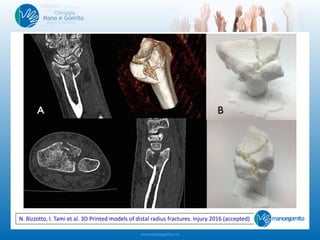

N. Bizzotto, I. Tami et al. 3D Printing of bone fractures:

a new tangible realistic way for preoperative planning and education. Surg. Innov. 2015

N. Bizzotto, I. Tami et al. 3D Printed models of distal radius fractures. Injury 2016 (accepted)